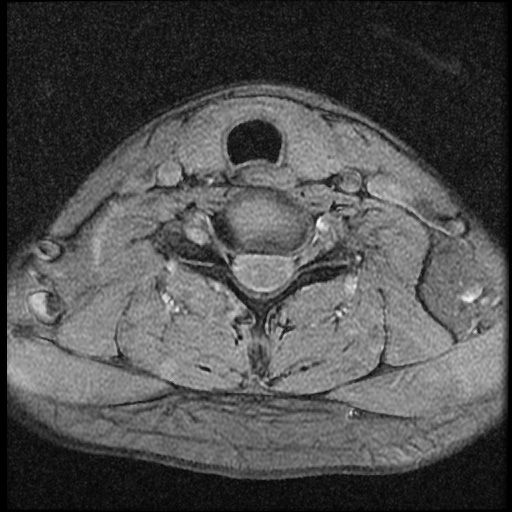

이 MRI 사진은 21년도 사고 당시 찍은 MRI 사진 입니다. 확인 부탁드립니다~

전체 mri를 다 봐여겠지만 보여주신 mri 컷에서는 의미있는 경추 디스크탈출이 보이지 않습니다.